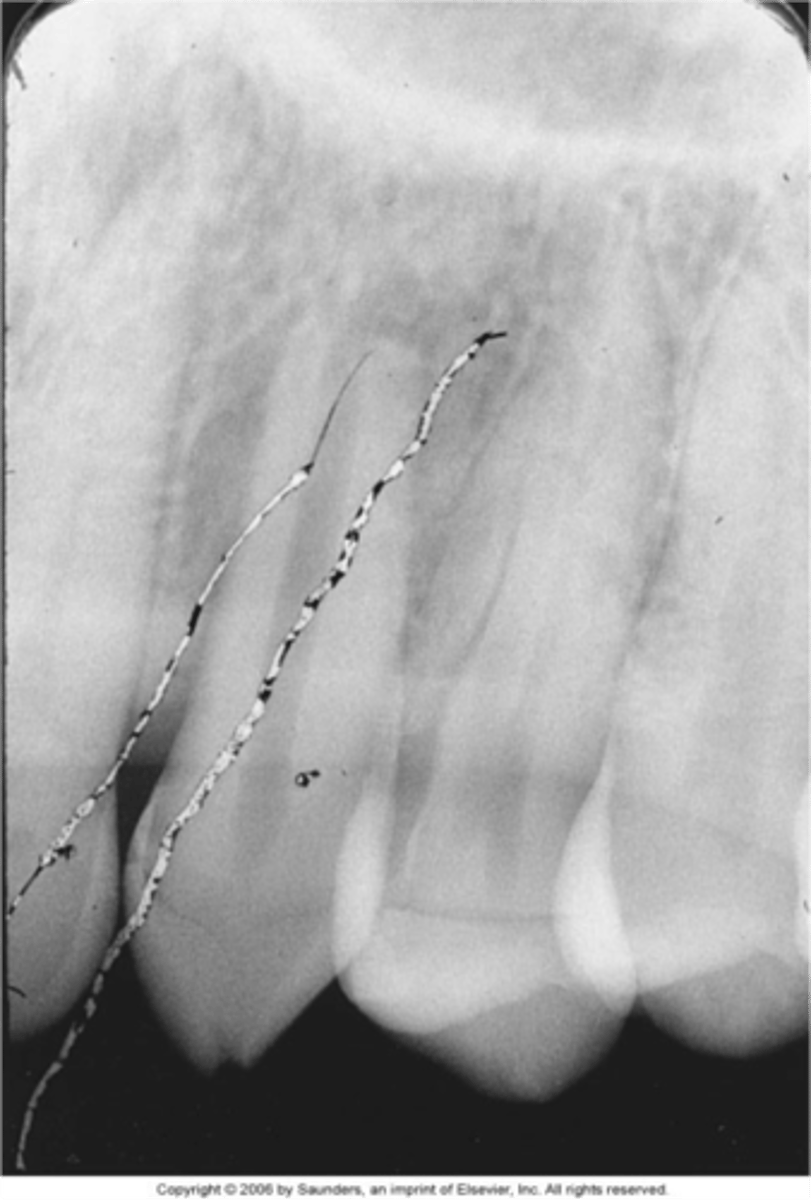

Reverse film-herringbone

Film bend